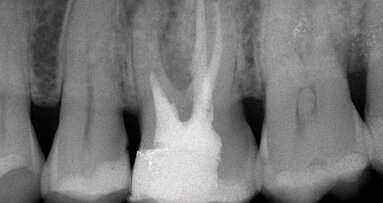

Il sistema MAP (Micro-Apical Placement System) è un carrier straordinario ed efficace per il posizionamento di precisione dei materiali per otturazione endodontica mediante approccio ortogrado o retrogrado.

Questo sistema professionale intelligente è considerato il prodotto d’elezione per terapie di perforazione, otturazione apicale, incappucciamento pulpare e otturazione retrograda. Gli aghi in NiTi a memoria di forma possono essere modellati manualmente con qualsiasi curvatura richiesta e si adattano facilmente alla forma del canale radicolare per un posizionamento efficace dei materiali di riparazione.

Il sistema MAP è disponibile in vari kit ed è composto da una siringa in acciaio inossidabile di qualità svizzera con innesto a baionetta progettata per l’impiego con una vasta gamma di aghi intercambiabili. Gli aghi classici con angolazione singola sono destinati a procedure endodontiche non chirurgiche di precisione, mentre gli aghi da chirurgia con tripla angolazione sono più indicati per le procedure endodontiche chirurgiche. Gli aghi in NiTi con memoria di forma hanno un design universale, ideale per terapie ortograde e retrograde. I pistoni sono riutilizzabili e realizzati in poliossimetilene (POM) di grado medico. Il materiale residuo all’interno degli aghi è facilmente asportabile mediante curette per pulizia in NiTi.

In associazione con PDTM MTA White, l’esclusivo cemento a base di minerale triossido aggregato appositamente sviluppato per essere applicato con questo carrier, il sistema MAP offre ai professionisti dentali una soluzione perfetta, semplicissima e della massima durata, per terapie endodontiche predicibili e di successo.